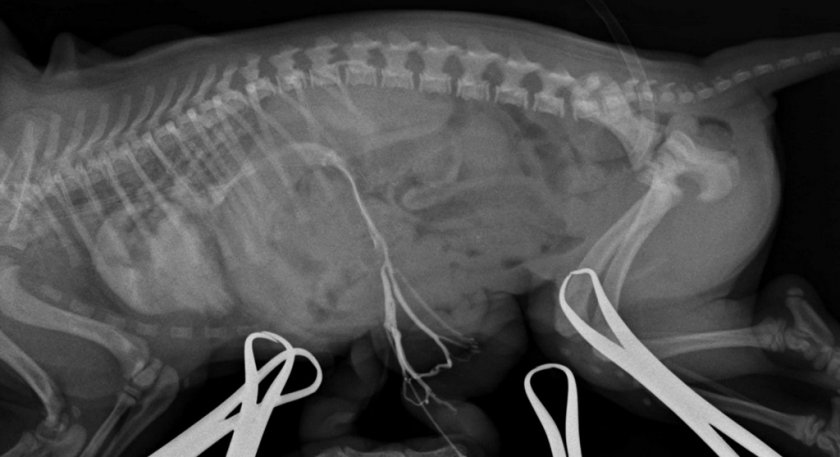

- Ренгенография. Зачастую назначается животным с печёночными шунтами или при терминальной стадии цирроза, благодаря чему удаётся установить уменьшение печени в размерах.